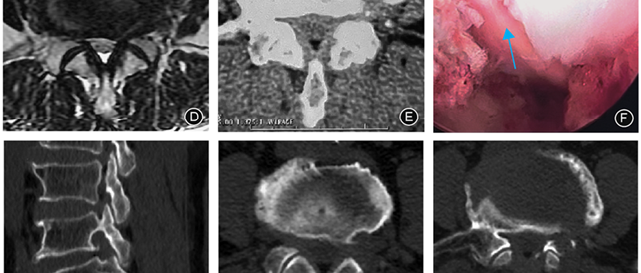

点击标题下「蓝色微信名」可快速关注文章来源:中华骨科杂志, 2023,43(2) : 81-88作者:徐宝山 张凯辉 田和顺 黎宁 许海委摘要 目的探讨椎间孔外入路单侧双通道内镜(unilateral biportal endoscopy,UBE)在治疗椎管外腰骶神经根卡压症中的应用。方法回顾性收集2020年1月至2022年3月在天津医院采用椎间孔外入路UBE治疗椎管外腰骶神经根卡压症17例,男9例、女8例,平均年龄为59.2岁(范围45~71岁)。17例患者均有下肢放射性疼痛、麻木、无力,伴或不伴间歇性跛行。MRI示L...